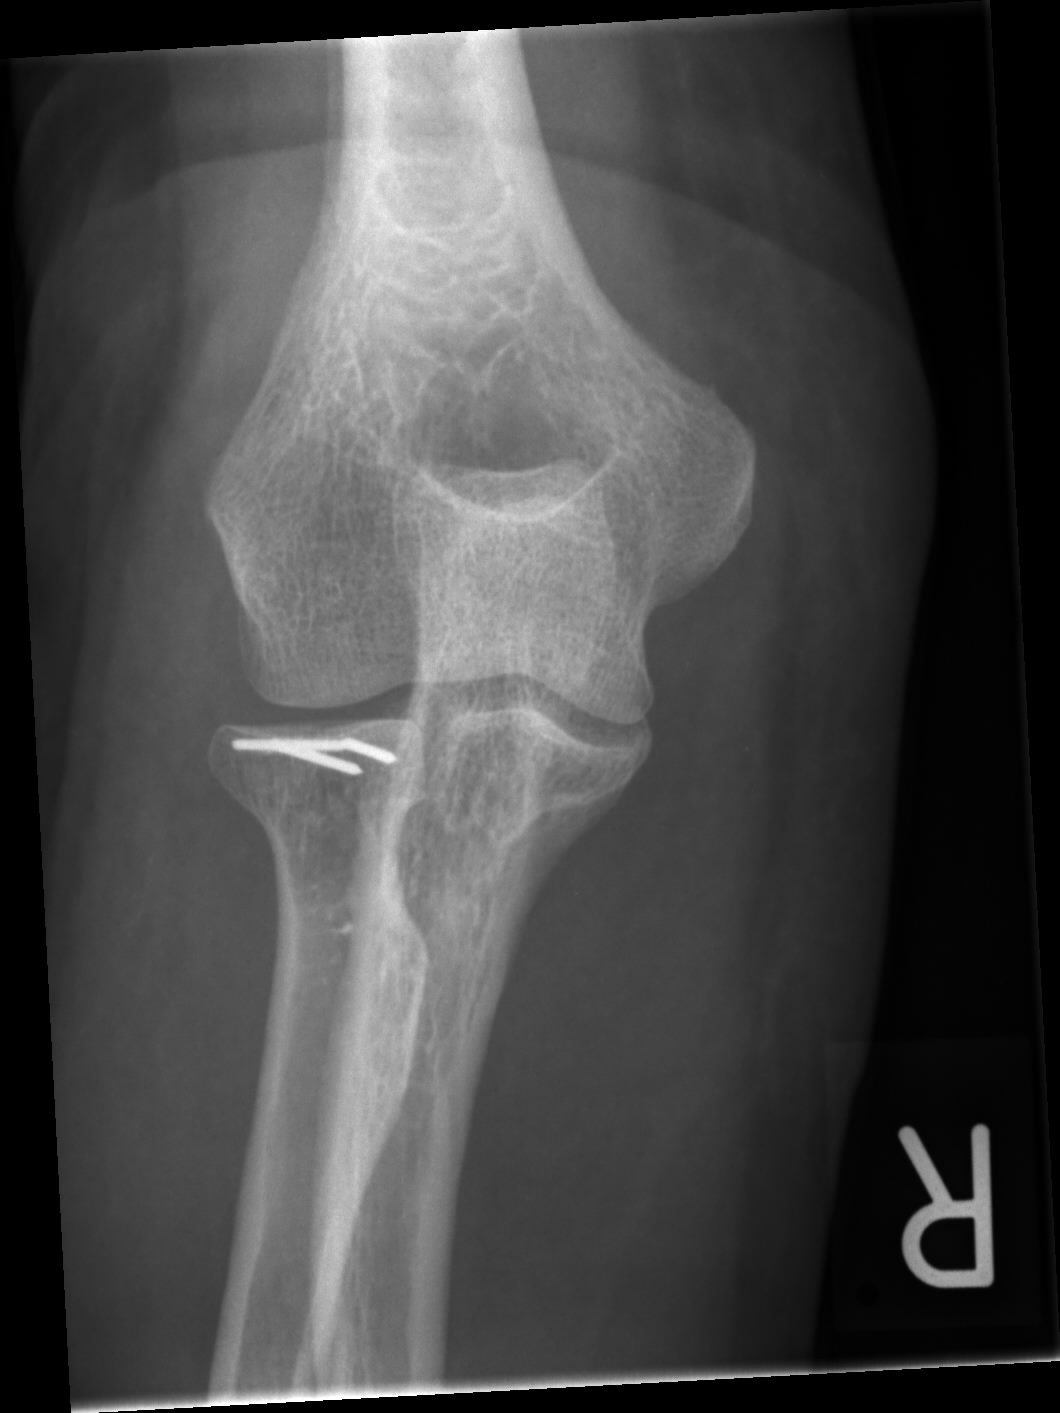

Radiusköpfchenfraktur: Symptome, Diagnose und Behandlung ...

Radiusköpfchenfraktur: Symptome, Diagnose und Behandlung ... from gelenk-klinik.de

Radiusköpfchenfraktur

Radiusköpfchenfraktur from www.dr-gumpert.de